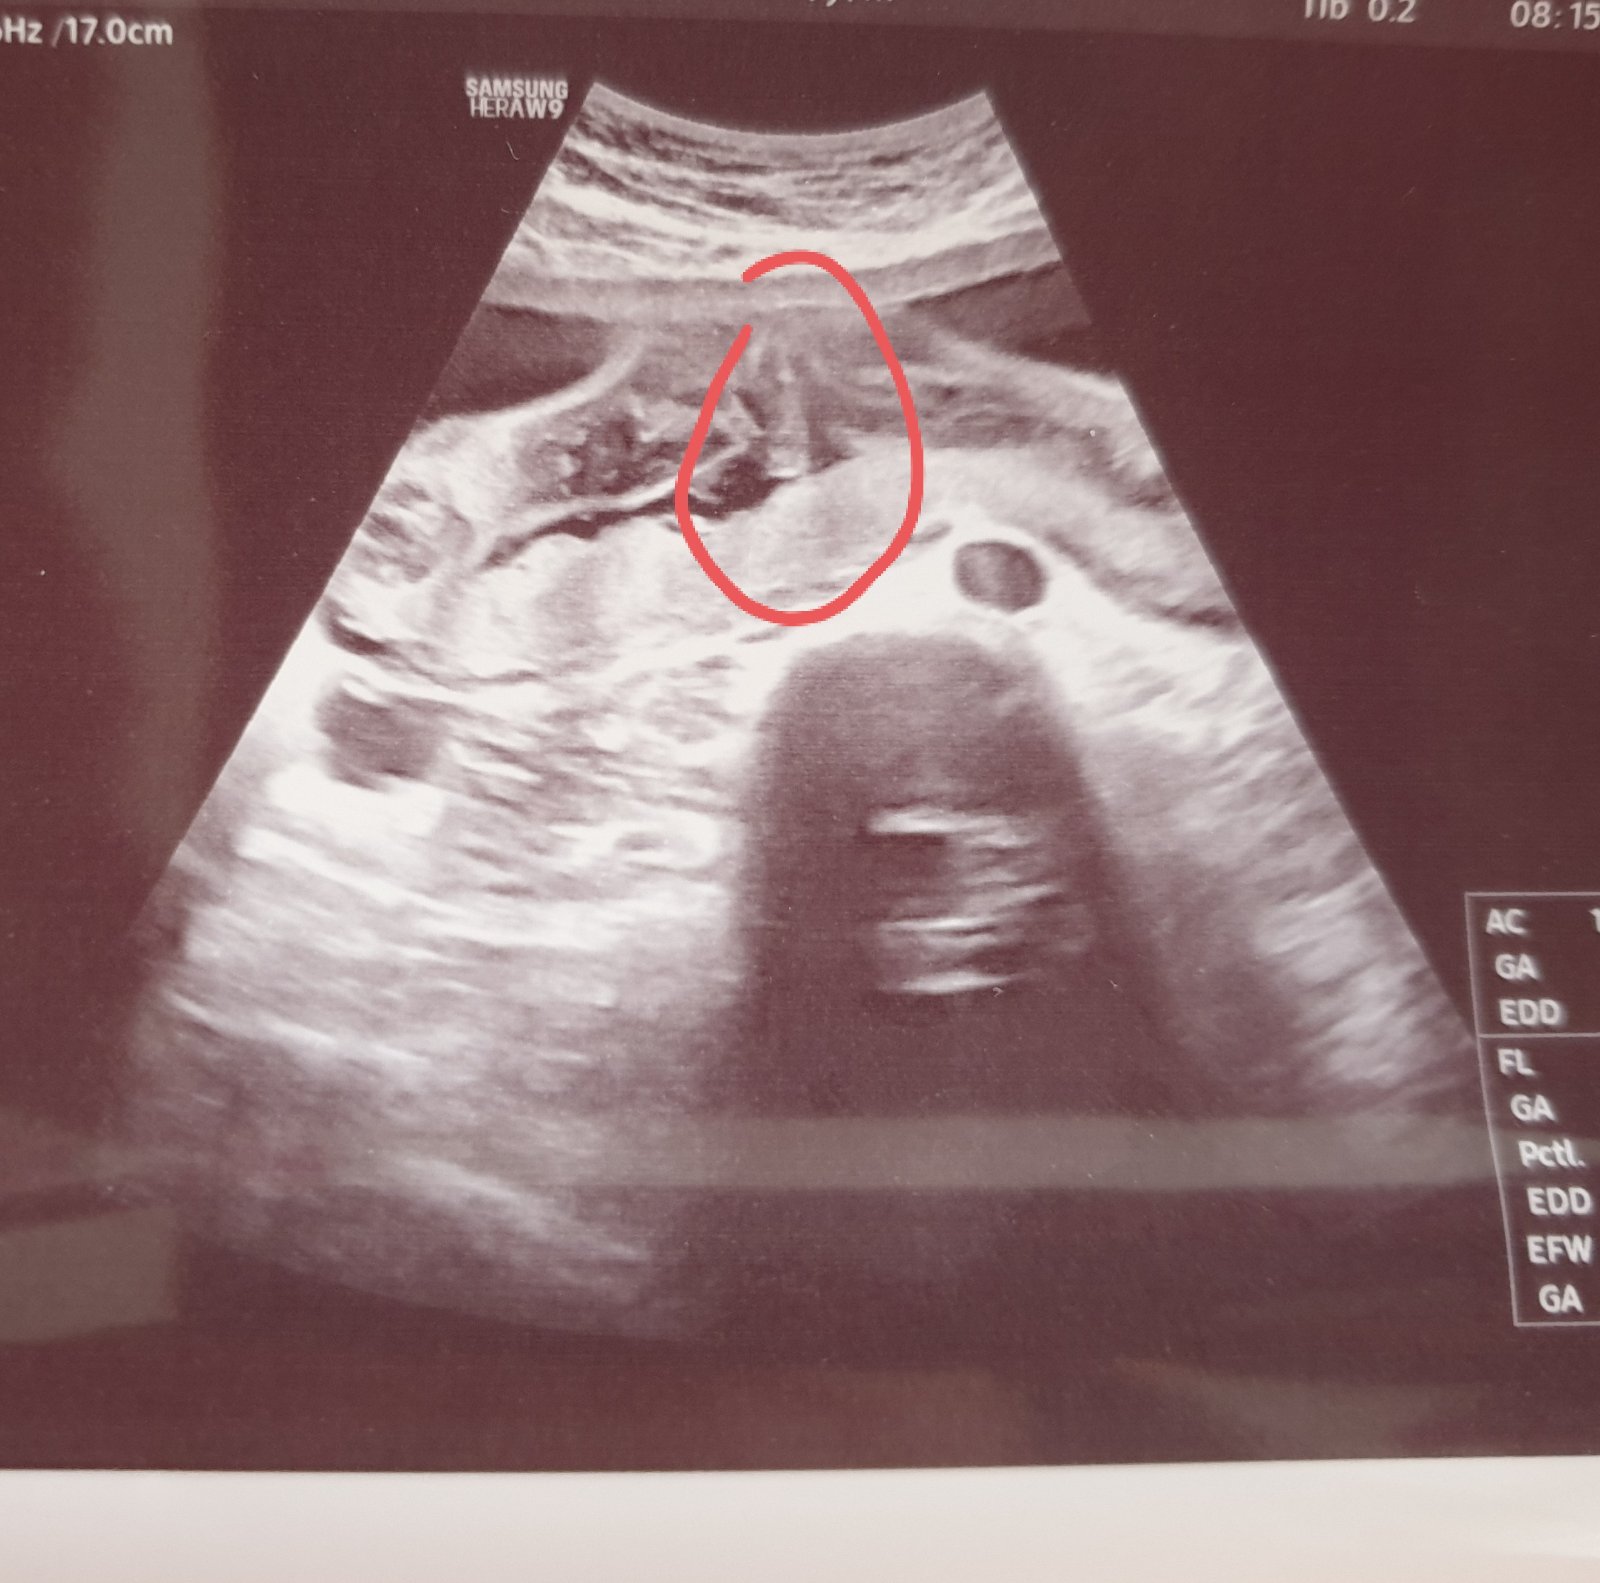

Co vidíte na ultrazvukové fotce ve 22. týdnu?

Nevím, jestli tam mám vidět piňďulu nebo čárku 🤷♀️😅

Co vidíte na fotce vy? 😊

No ja nejsem odbornik,ale na utz sem u nas videla jasne kávove zrnko, (|) opravdu takto... tady to nevidim :D

Já si myslím chlapeček. Nemáte fotku z profilu z prvního screeningu?

Myslím, že holka, nevidím tam varlata a to uprostřed mi přijde jako pupeční šňůra.

Asi holčička. Nic navíc tam nevidím. A jinak je ten dr. pěknyýblbec, teda.